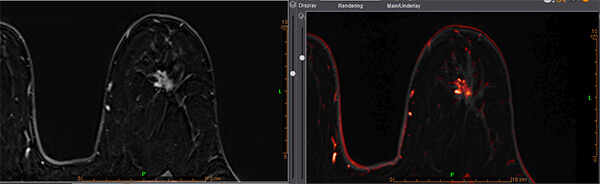

Τρισδιάστατη απεικόνιση ταχείας πρώιμης αιμάτωσης μαστών

- Δυναμική αγγειογραφία (4D time resolved TWIST)

- Επεξεργασία των δεδομένων σε σύστημα CAD